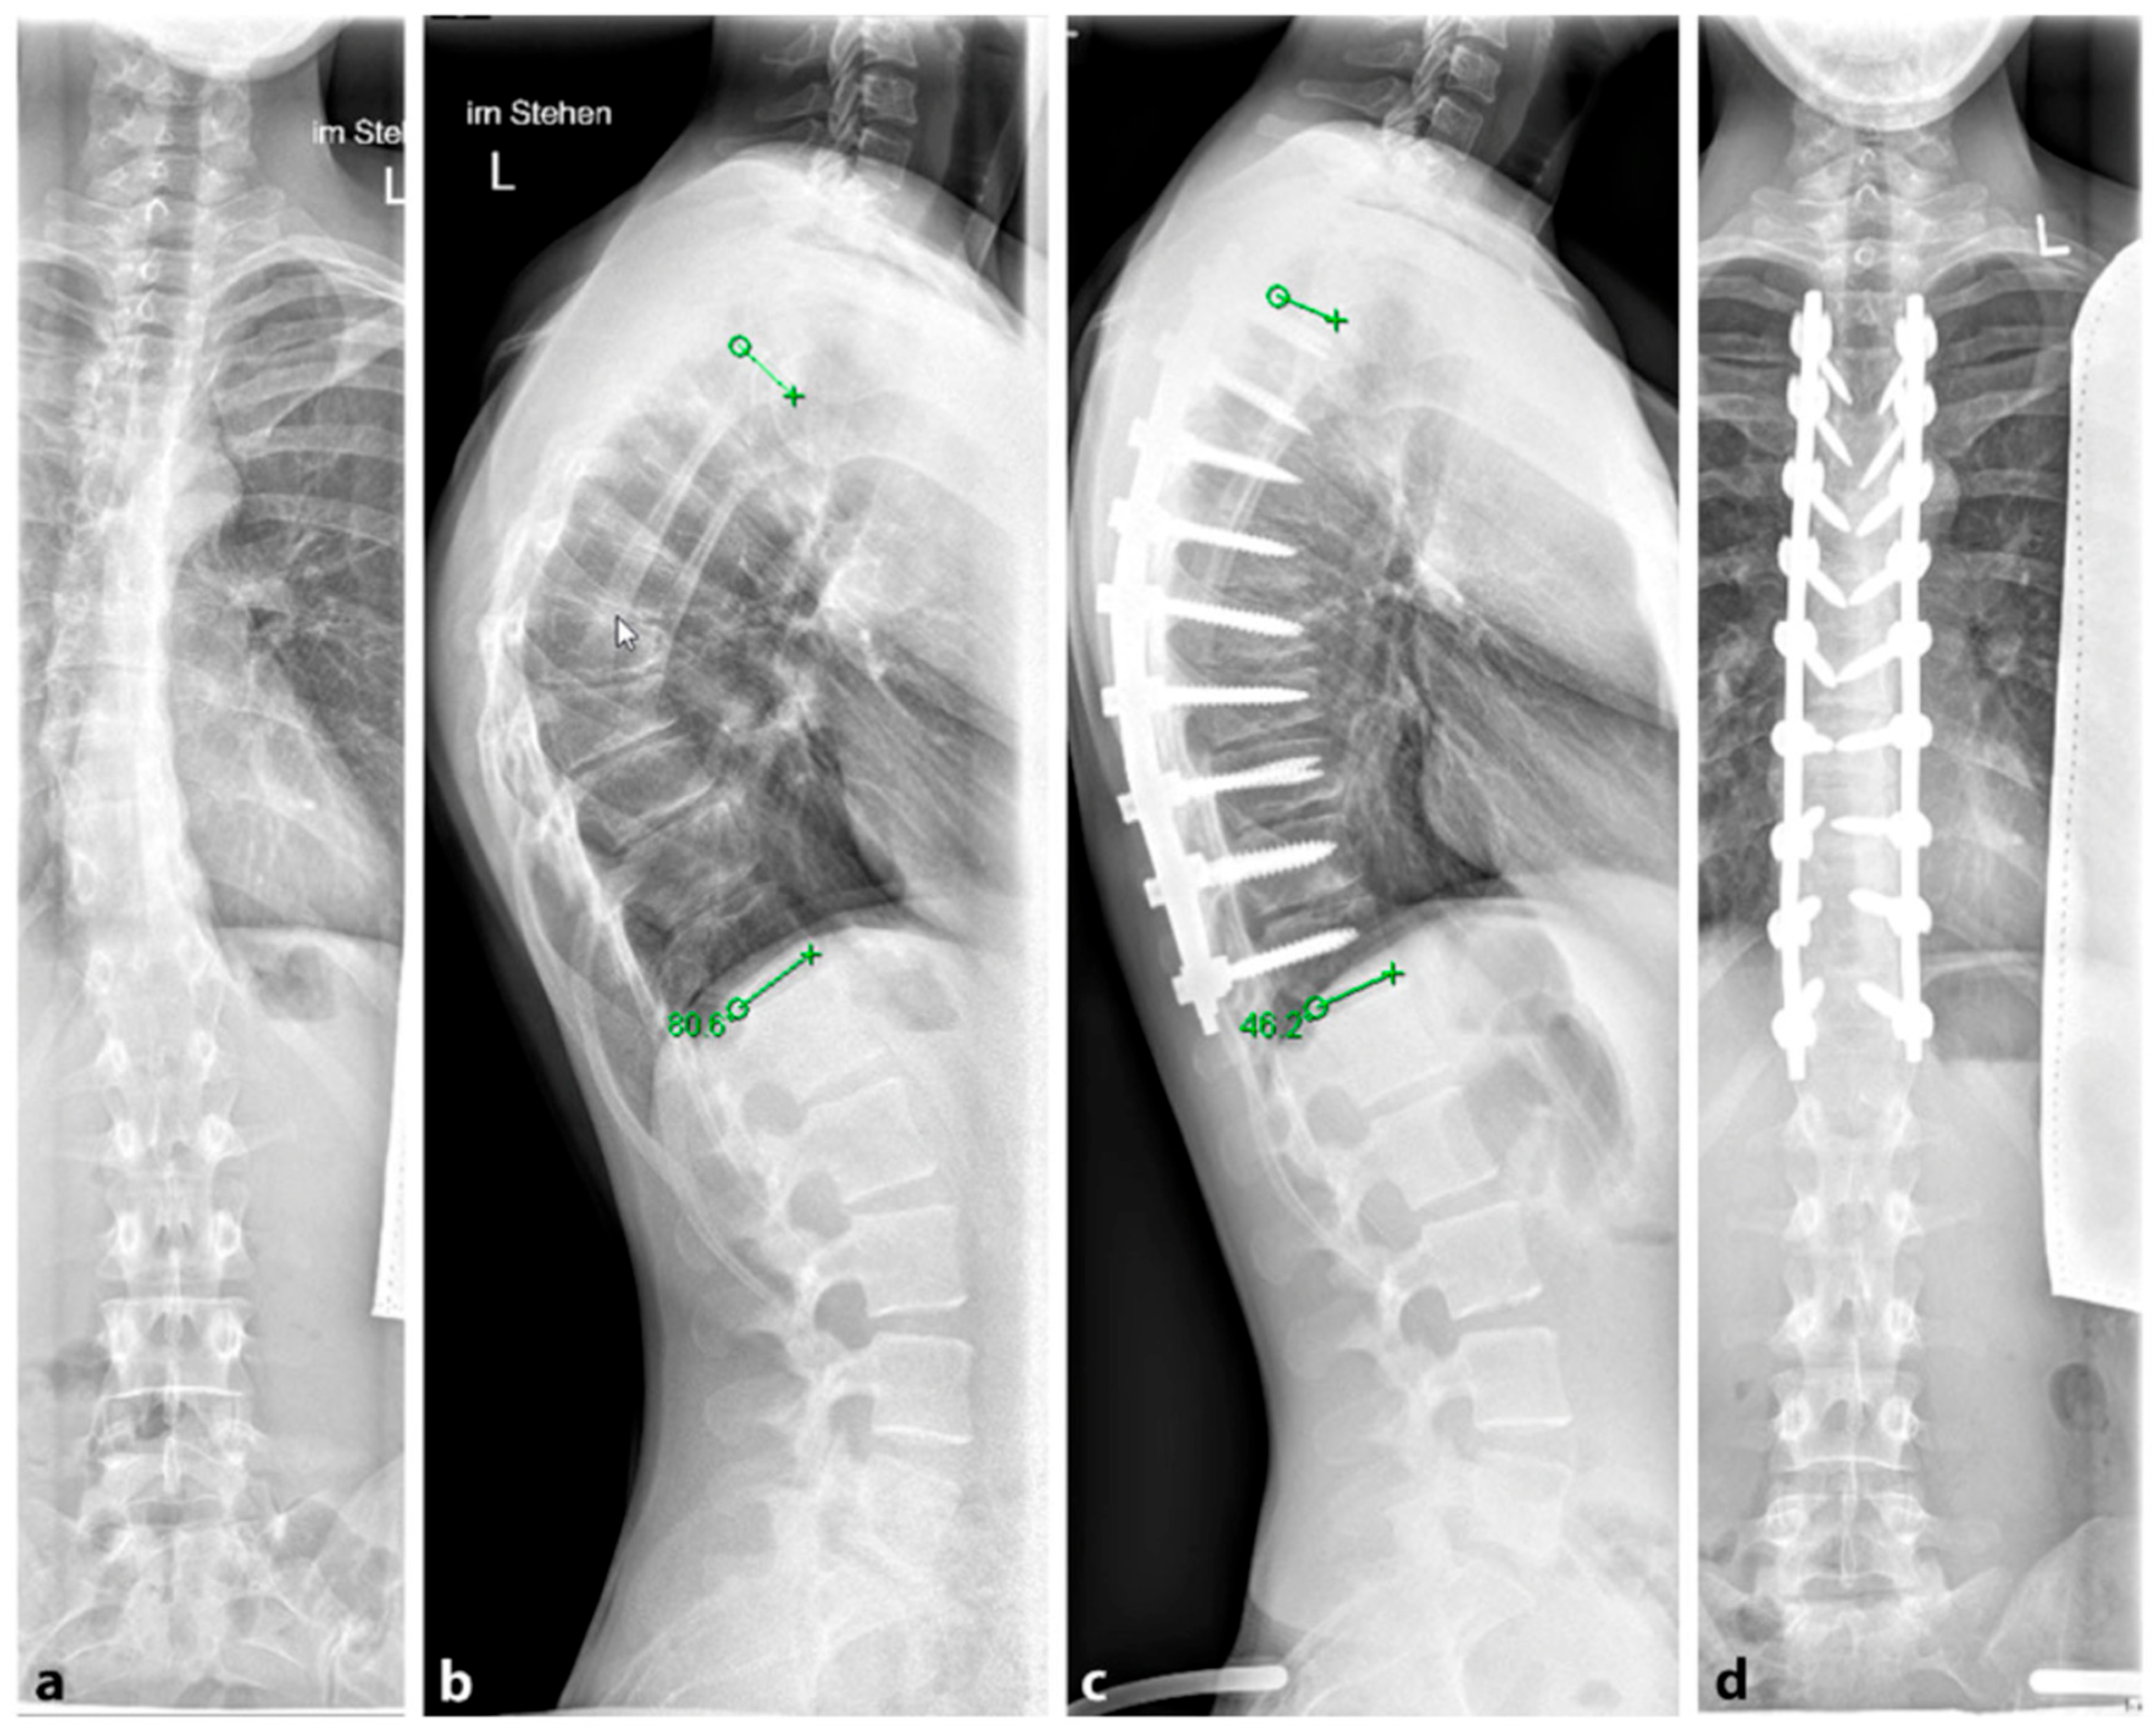

Figure 4. (a,b). Preoperative representation of the scoliosis and (c,d). Postoperative image following expansion thoracoplasty and implantation of the vertical expandable prosthetic titanium rib (VEPTR), attached proximal to the rib and distal to the laminae (reprinted with permission [10]).